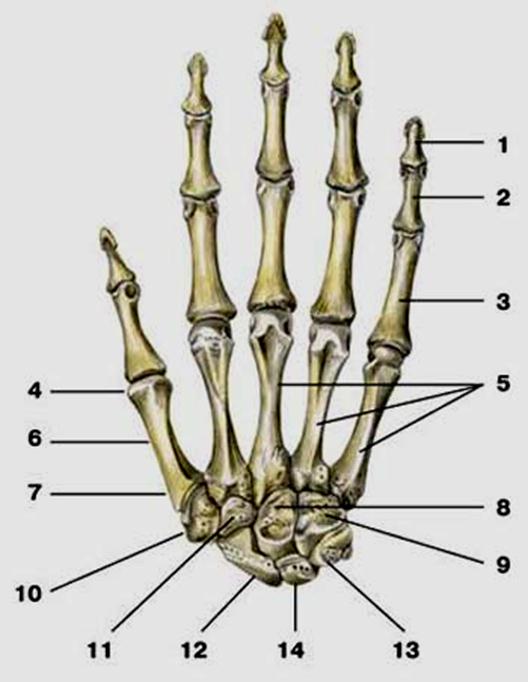

S: Числом 10 обозначена os ### (латинский язык).

S: Цифра 5 обозначает ossa ### (латинский язык).

S: Цифрой 8 обозначена os...

S: Числом 12 обозначена os...

S: Числом 13 обозначена os...

S: Цифра 3 указывает на...

S: Цифра 2 указывает на …

S: Цифра 1 указывает на....